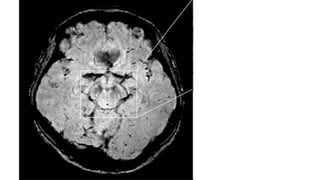

SWALLOW TAIL SIGN

The swallow tail sign describes the

normal axial imaging appearance of

nigrosome-1 within the substantia

nigra on high resolution T2*/SWI

weighted MRI

Absence of the sign (absent swallow tail

sign) is reported to have a diagnostic

accuracy of greater than 90%

for Parkinson disease